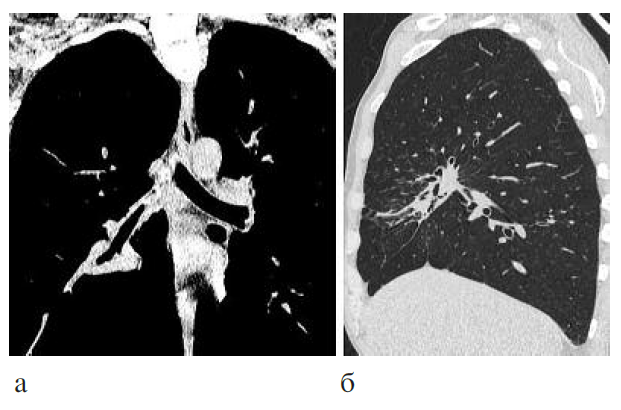

Клинический диагноз: ВИЧ-инфекция, 4В стадия, фаза прогрессирования вне АРТ. Генерализованный туберкулез: туберкулез внутригрудных лимфатических узлов, правого главного, промежуточного и среднедолевого бронхов, диссеминированный туберкулез легких, правосторонний экссудативный плеврит, туберкулез внутрибрюшных и забрюшинных лимфатических узлов, туберкулез периферических лимфатических узлов, МБТ+, ШЛУ, распространенный висцеральный кандидоз, манифестная цитомегаловирусная инфекция, хронический вирусный гепатит С, наркомания. Уровень CD4+ лимфоцитов 186 кл/мкл, вирусная нагрузка более 1 млн копий/мл, в мокроте ДНК МБТ с лекарственной устойчивостью к рифампицину. Начата противотуберкулезная химиотерапия по IV режиму. Переносимость лечения неудовлетворительная (гепатотоксическая реакция). При рентгенологическом обследовании отмечено объемное уменьшение правого легкого, в верхней доле на фоне фиброза полость распада размером 3,8¥2,2 см с толстыми неровными стенками, очаги диссеминации в обоих легких (рис. 3). В течение первого месяца лечения отрицательная клиническая динамика, получен результат посева мокроты, выявлена ШЛУ МБТ к изониазиду, рифампицину, стрептомицину, канамицину, каприомицину, офлоксацину. Назначен V режим химиотерапии с включением линезолида, бедаквилина, азитромицина, моксифлоксацина, протионамида, теризидона, этамбутола. Через 2 мес лечения присоединена АРТ. Через 6 мес терапии по новому режиму отмечены прекращение бактериовыделения и выраженная положительная клинико-рентгенологическая динамика (рис. 4). Больной выписан для продолжения лечения в амбулаторных условиях, в последующем в течение 2 лет рецидива туберкулеза не отмечено. Данное наблюдение показывает возможность эффективного лечения больного коинфекцией ВИЧ/туберкулез с использованием новых режимов химиотерапии.

Рис. 3. КТ-исследование до лечения: а – увеличенные казеифицированные внутригрудные лимфатические узлы; б – перибронхиальная инфильтрация и лимфогенная диссеминация легочной ткани; в – увеличенные казеифицированные внутрибрюшные лимфатические узлы.